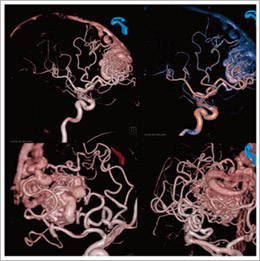

図2 AVM(造影)

DynaCT/DSAによるVR画像